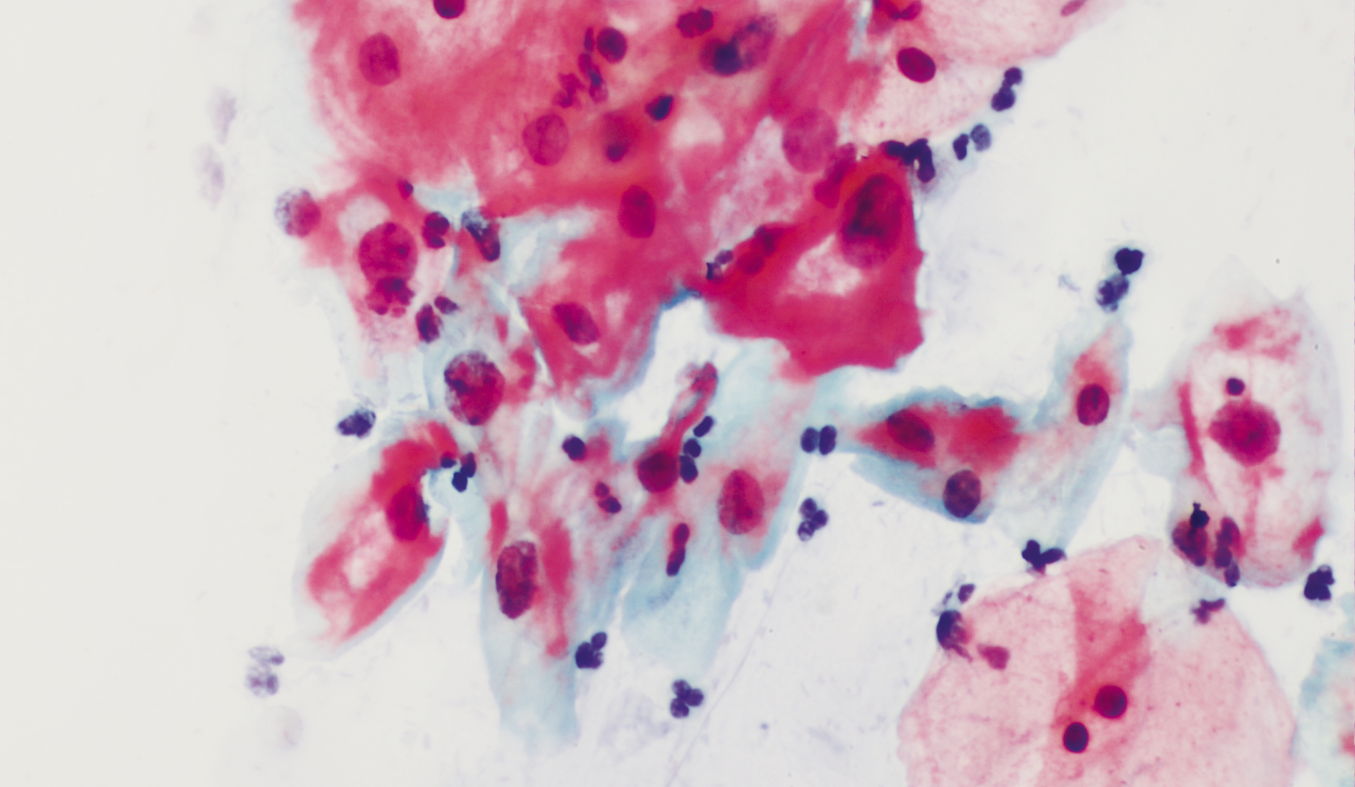

Eosinophilic, mature dyskaryotic cells and koilocytes of squamous epithelium in a 28-year-old patient.

CIN 1. p16&Ki67